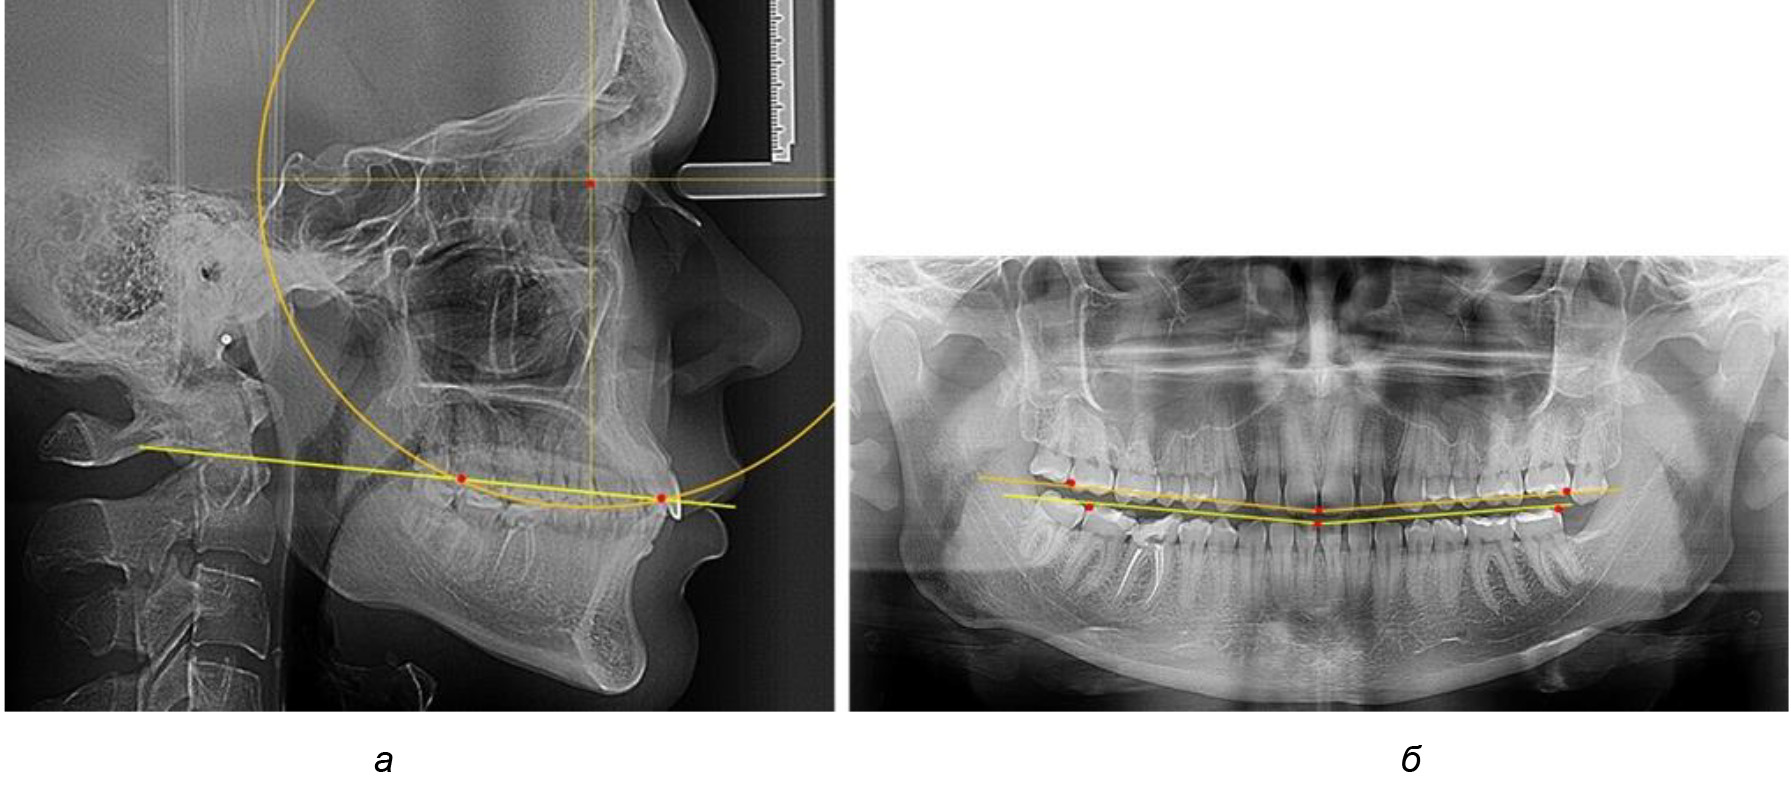

Таким образом, проведенное лечение техникой «прямой» дуги способствует нормализации окклюзионного равновесия и торку передних зубов, однако не соответствует оптимальному окклюзионному статусу, характеризующему физиологическую окклюзию. При этом величина нижнечелюстного угла оставалась на прежнем уровне (рис. 5).

Рис. 5. Особенности ТРГ при патологической кривой Spee до лечения (а) и после лечения (б) техникой «прямой» дуги

После лечения пациентов техникой «прямой» дуги, так же как и в 1-й подгруппе, было отмечено увеличение сагиттального размера окклюзионной лини в среднем на (2,38 ± 0,83) мм. Окклюзионная линия практически касалась окклюзионного контура всех жевательных зубов, и отмечалось практически полное отсутствие кривой Spee, так же как и у людей 1-й подгруппы 2-й группы (рис. 6).

Рис. 6. Особенности ТРГ при оптимальной кривой Spee до лечения (а) и после лечения (б) техникой «прямой» дуги

Таким образом, проведенное лечение техникой «прямой» дуги способствует нормализации окклюзионного равновесия и торку передних зубов, однако не соответствует оптимальному окклюзионному статусу, характеризующему физиологическую окклюзию. При этом величина нижнечелюстного угла оставалась на прежнем уровне.